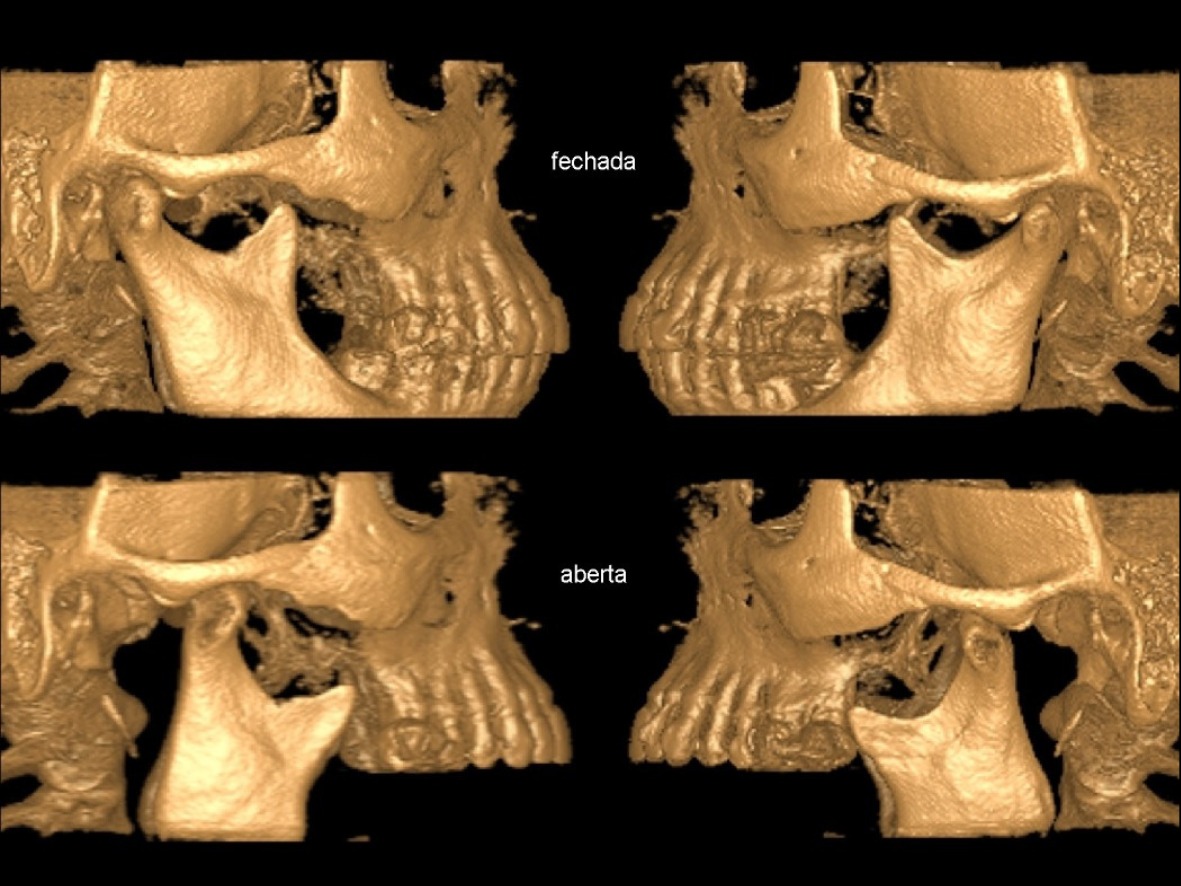

ATM

Exame da articulação temporomandibular, indicado para dores, estalos ou dificuldades ao abrir a boca.